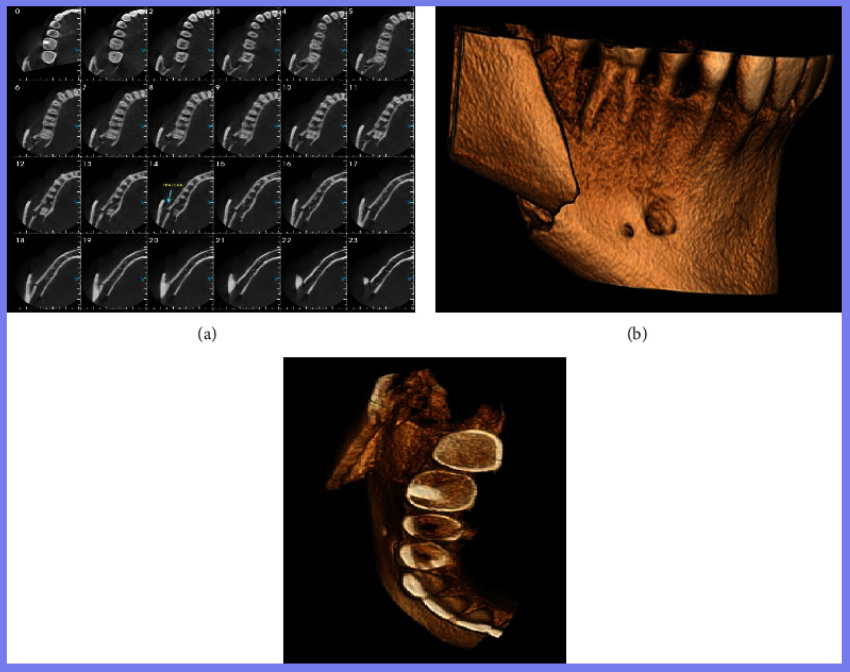

在医院对患者进行检查,除全身健康状况外,临床评估还显示右侧面部剧烈疼痛和肿胀、下颌轮廓明显凹陷、张口受限、咬合不正、前段骨性活动性差、右下颌第三磨牙缺失。计算机断层扫描 (CT) 扫描和 3D 重建分别显示直角部位下颌节段的牙槽骨连续性断裂和横向移位的髁突 (远端) 碎片。水肿消退后,在全身麻醉下进行下颌骨骨折治疗。外科医生进行口内切开复位,重新定位节段,并使用两块钛板和六毫米螺钉防止碎片移动并确保骨一期愈合。在同一手术中,对侧上下第三磨牙也被拔除。